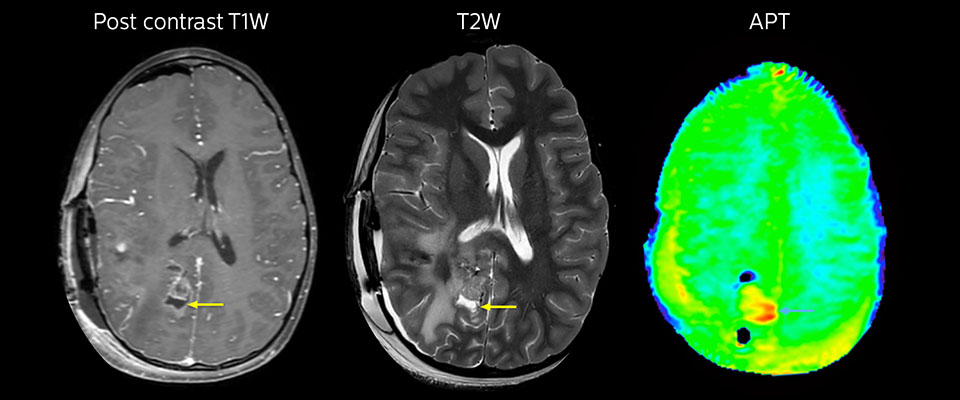

Large metastatic brain lesion

This 10-year-old patient underwent Ewing’s sarcoma tumor resection 7 years ago, but was found to now have a large metastatic lesion in the brain. This lesion shows clearly increased APT signal.

MRI with APT post resection

Immediately post resection MRI was again performed. T2-weighted and postcontrast T1-weighted images are quite inconclusive for distinguishing residual tumor tissue from postoperative tissue changes. On the APT image some high signal is still seen, which would suggest residual tumor tissue.